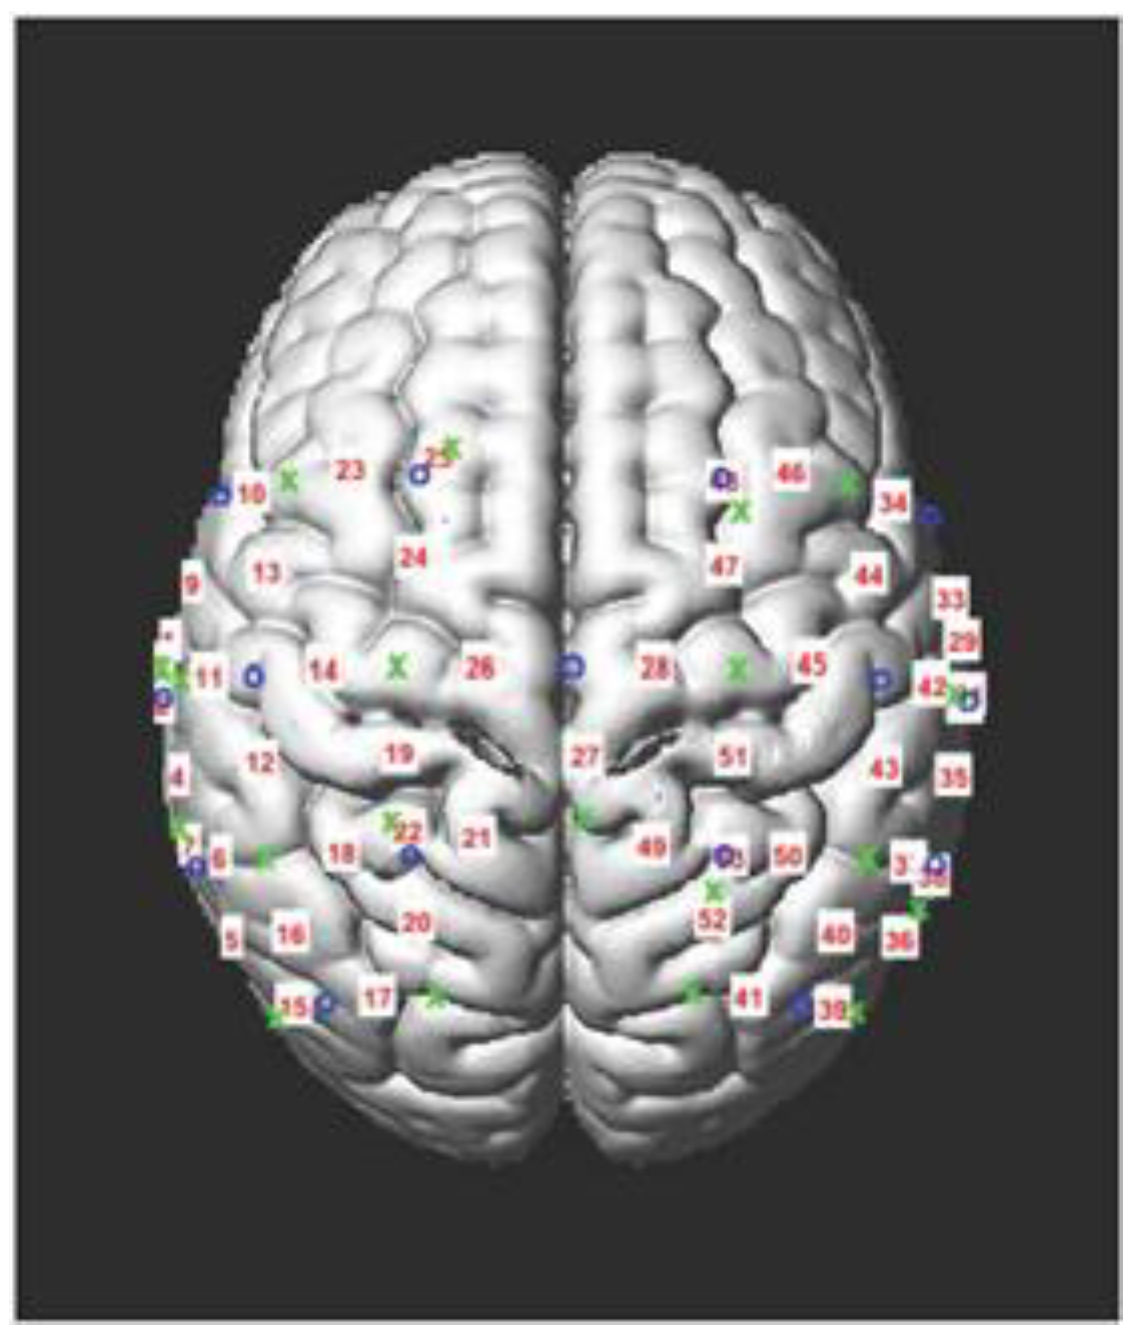

Functional Near-Infrared Spectroscopy (fNIRS) Acquisition with Concurrent Balance Testing: Balance performance and neural activity were evaluated simultaneously using a portable fNIRS device, the NIRSport2 (nirx.net), which can accommodate gross motor movements in more naturalistic environments. Participants were fitted with an appropriately sized cap that positioned optodes (i.e., near-infrared light sources and detectors) over bilateral motor cortices and inferior parietal sulci, as these regions are associated with balance [26]; see Figure 1 for optode placement.

Figure 1. fNIRS Data Acquisition. fNIRS optodes—light sources and light detectors—were placed over bilateral motor cortices and inferior parietal sulci to form 53 total channels (i.e., the intersection of a light source and detector), as depicted in this figure.